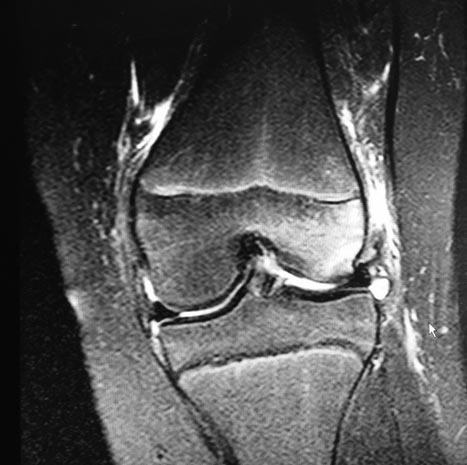

Сделать артроскопию и убрать фрагмент самый простой вариант, и к нему мы готовы.

Но фрагмент очень большой, размером с надколенник.

Можем сделать артроскопию и оценить состояние хряща и решить вопрос о фиксации?

У кого есть опыт фиксации больших хондральных дефектов винтом или швом?

Только сейчас присмотрелся - фрагмент крупный. Ложе на опорной поверхности мыщелка бедра. В послеоперационом периоде потребуется фиксированное сгибание под углом близким к 90 градусов. Нет опыта работы с детьми. Если продумать послеоперационную реабилитацию, то может быть...